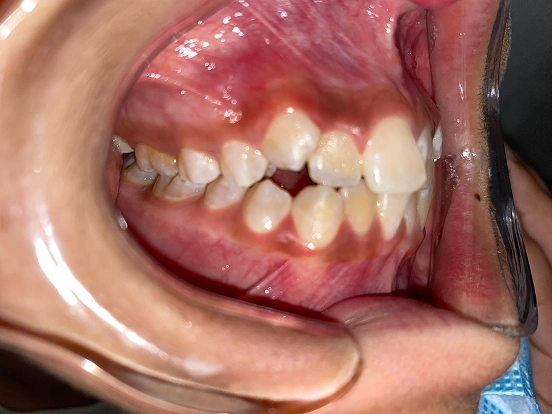

Braces GI

GI achieved a beautifully balanced smile through braces treatment. Over time, the brackets and wires gently moved each tooth into its ideal position, resulting in improved alignment, comfort, and confidence in their everyday smile.